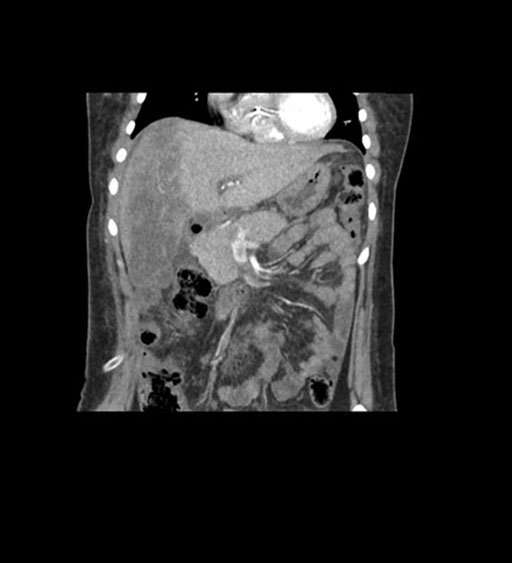

Coronal Arterial